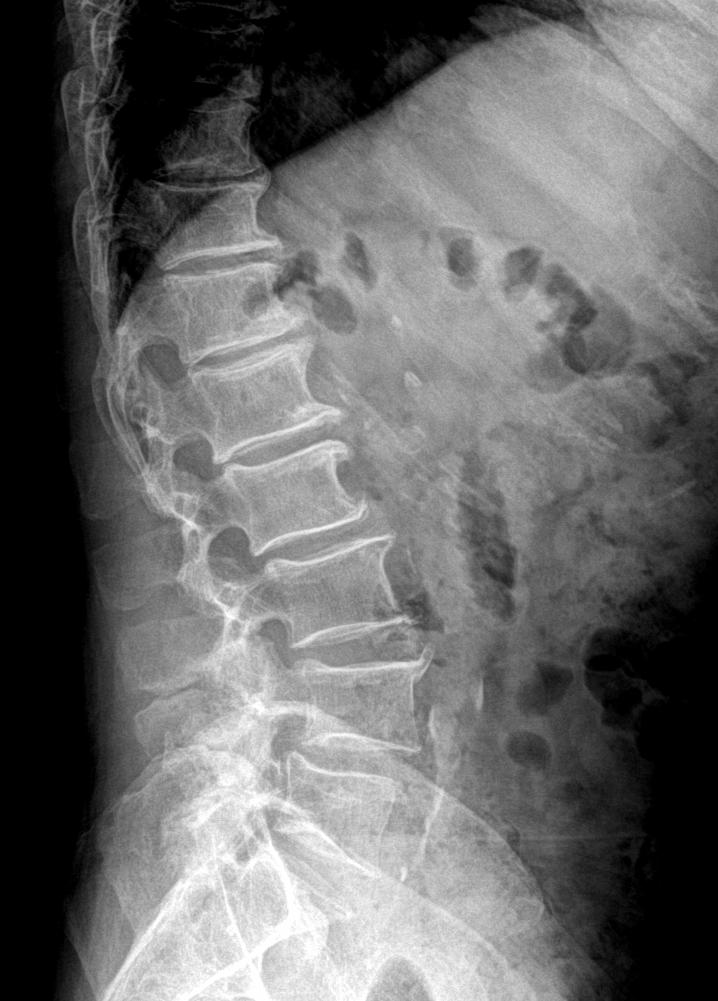

腰部疼痛